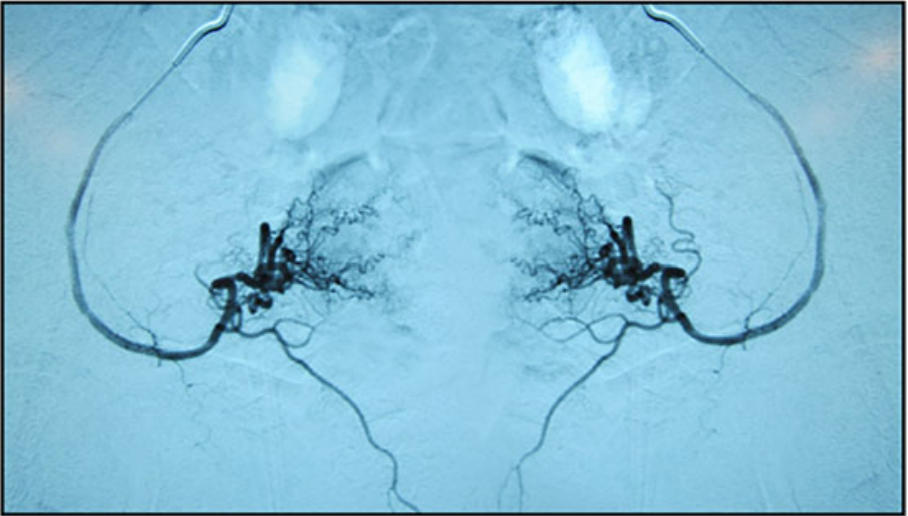

方 法:采用Seldinger技術經股總動脈入路,置入4F導管鞘,使用帶血管造影彎曲的Terumo 0.035英寸導引導管插管至雙側髂內動脈,經此導管引入2.5F微導管至子宮動脈遠端螺旋小動脈(下圖),確認位置穩(wěn)定后,經每條子宮動脈注入15 cm3細胞懸液(平均123.56*10?個細胞)。